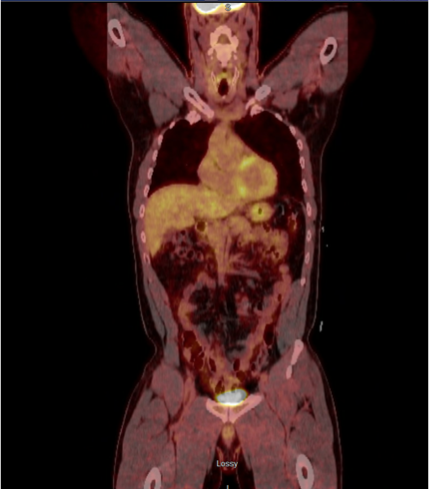

FDG-PET.jpg)